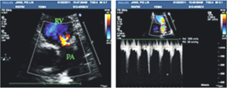

三個月後超音波,中度肺動脈狹窄